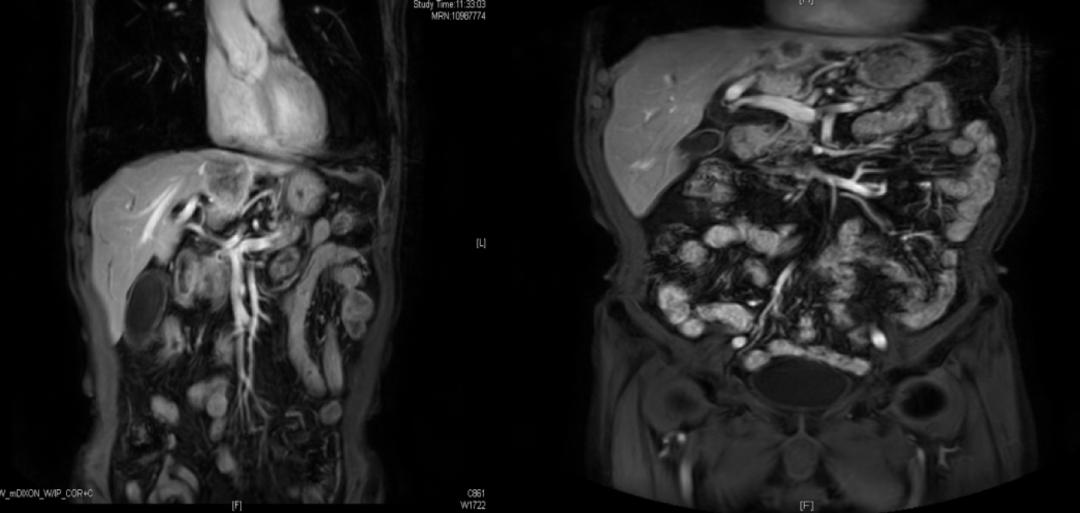

放射治疗及靶向治疗---疗效评价:

首诊10.28(左):42mm*31mm;四治疗后3.10(右):20.8mm*12.9mm明显缩小

放疗结束MR报告:2021-1-9PET-MR示“鼻咽部黏膜增厚伴糖代谢增高,考虑肿瘤治疗后部分活性残留,枕骨斜坡、蝶骨体及梨骨后缘骨质破坏合并糖代谢增高,考虑肿瘤活性残留;双侧颈部未见高代谢淋巴转移影像改变;肝左叶S2结节伴糖代谢局灶性增高,考虑转移瘤”。

予行肝转移灶射波刀治疗。

疗效评估:接近CR